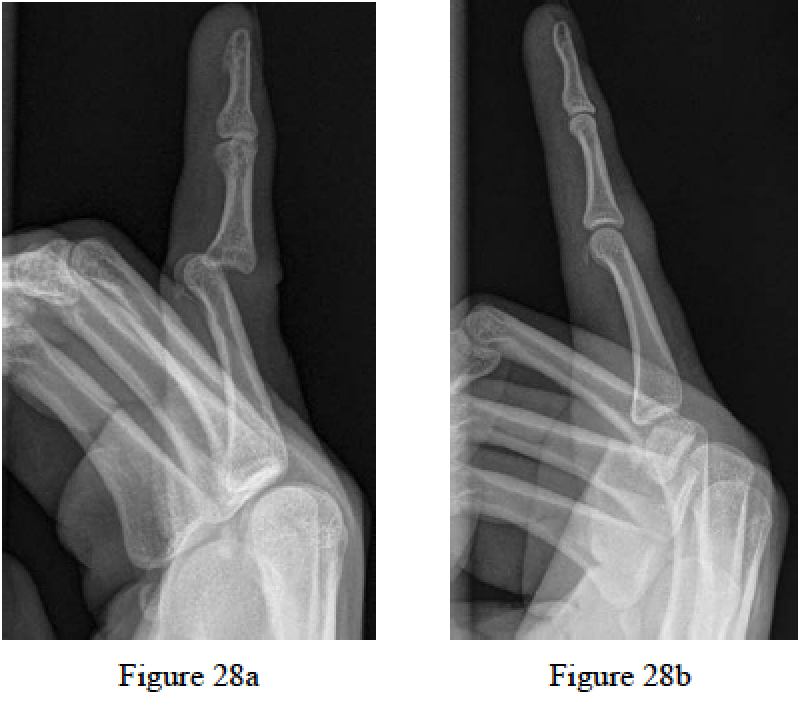

Merrel G, Slade JF. Dislocations and ligament injuries in the digits. In: Wolfe SW, Hotchkiss RN, PedersonWC, Kozin SH, eds. Green’s Operative Hand Surgery. 6th ed. Philadelphia, PA: Elsevier Churchill Livingstone; 2011:291-295.

Morgan WJ, Slowman LS. Acute hand and wrist injuries in athletes: evaluation and management. J Am Acad Orthop Surg. 2001 Nov-Dec;9(6):389-400. Review. PubMed PMID: 11730330.